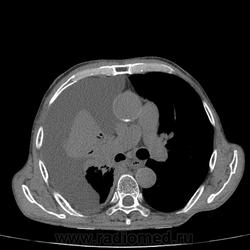

Пожилой мужчина, лечился по н/д правостороннней пневмонии в терап/отделении. Жалобы на одышку, кашель. По результатам Р-контроля после лечения направлен на КТ легких с диагнозом: плеврит справа, распад? В корне правого легкого вижу объёмное образование, с распадом. Смущают размеры плеврита,очень много жидкости, почти до 3 ребра. Анализы крови спокойные- L4,0-6,6, СОЭ 12-16мм. Неужто ТБС, отсев бы был при таком огромном поражении. В посеве мокроты-100% высев клебсиэллы пневмоние. Мокрота на общий анализ в работе-собирает с трудом, изза отсутствия мокроты. Плевральную пункцию еще не проводили. Н азначила бронхоскопию и плеврал пункцию. Как думаете, уважаемые коллеги, это онкопроцесс или тбс распад?

Самое интересное забыла показать- может это 100% навеет на мысль об опухолевом процессе, остеолитическая деструкция позвонка?

Не смотря дайкомы, только по рентгенограмме, предположил бы центральный рак правого легкого. Потому что большой гидроторакс, без смещения средостения в здоровую сторону, как правило, соответствует раковому ателектазу.

Коллеги, распада там нет, это вас медиастинальное окно подвело. В грудине тоже все в порядке. Да и компрессия позвонка "старая".

Небольшое количество увеличенных лимфоузлов, и те - не сказать, чтоб были очень крупными. От эмпиемы до онкологии... Умеренное количество жидкости в перикарде, толщиной слоя до 13-14 мм. При подобной картине не вижу смысла гадать по сжатому лёгкому, пишу так: массивный выпот справа, около 2500 мл, диафрагма оттеснена жидкостью каудально, печень (!!!) смещена каудально и вправо. Легкое справа значительно компрессировано жидкостью, оценка проходимости бронхов и состояния легочной паренхимы (кроме имеющейся эмфиземы) практически невозможна. Необходима пункция плевральной полости справа (цитология, ВК, посев на микрофлору и проч), КТ-контроль после эвакуации жидкости.